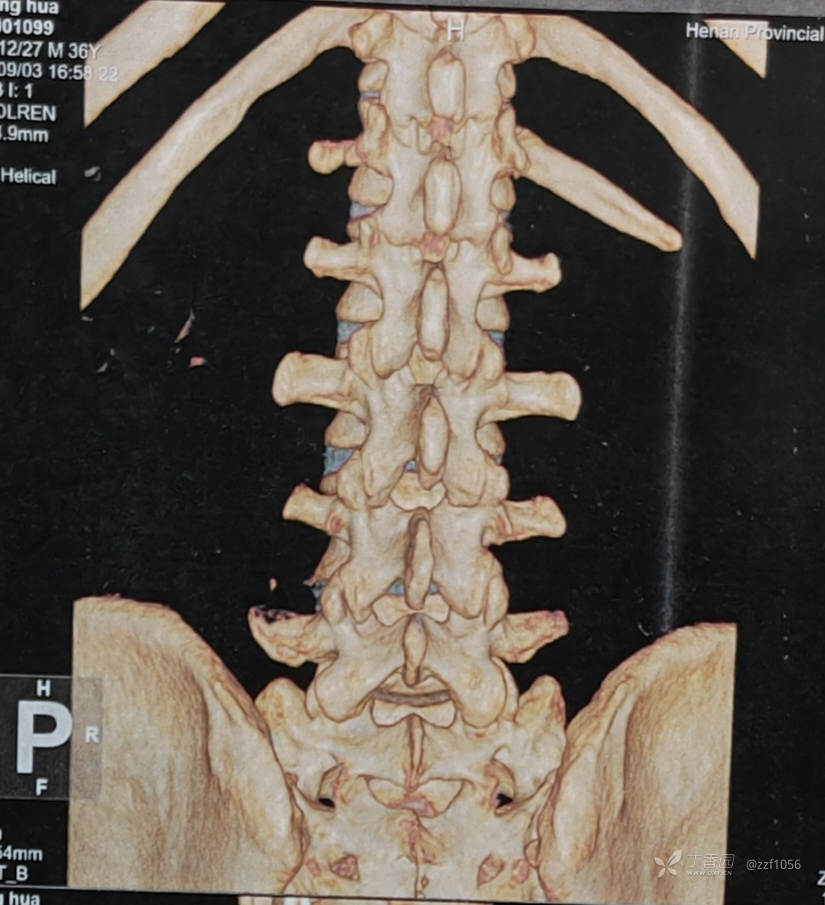

肋骨够数吗?

L1还是T12,三长四短五肥大

脱出明显

左侧,貌似两块

探讨:继续孔镜吗?

UBE还是Dalta

椎板间定位